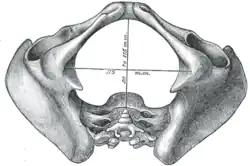

- Diameters of pelvic inlet

A distinction is made between the lesser or true pelvis inferior to the terminal line, and the greater or false pelvis above it. The pelvic inlet or superior pelvic aperture, which leads into the lesser pelvis, is bordered by the promontory, the arcuate line of ilium, the iliopubic eminence, the pecten of the pubis, and the upper part of the pubic symphysis. The pelvic outlet or inferior pelvic aperture is the region between the subpubic angle or pubic arch, the ischial tuberosities and the coccyx. [3]